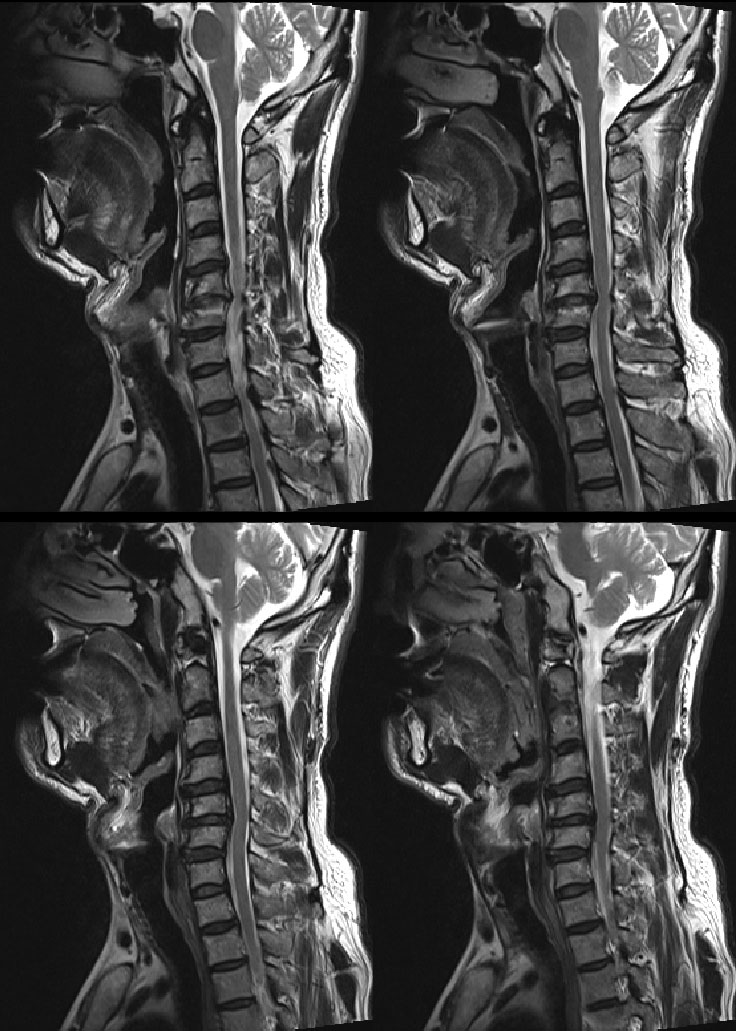

..* mri Դϴ.. 1⵿ ̷ ġῡ ڸ ũ Ƿ, , , , Ҹ ߵǴ MRI ·μ ƴ 1 ġص 1 ġؾ Ѵٴ Դϴ. mri Ͻð ص帮. |